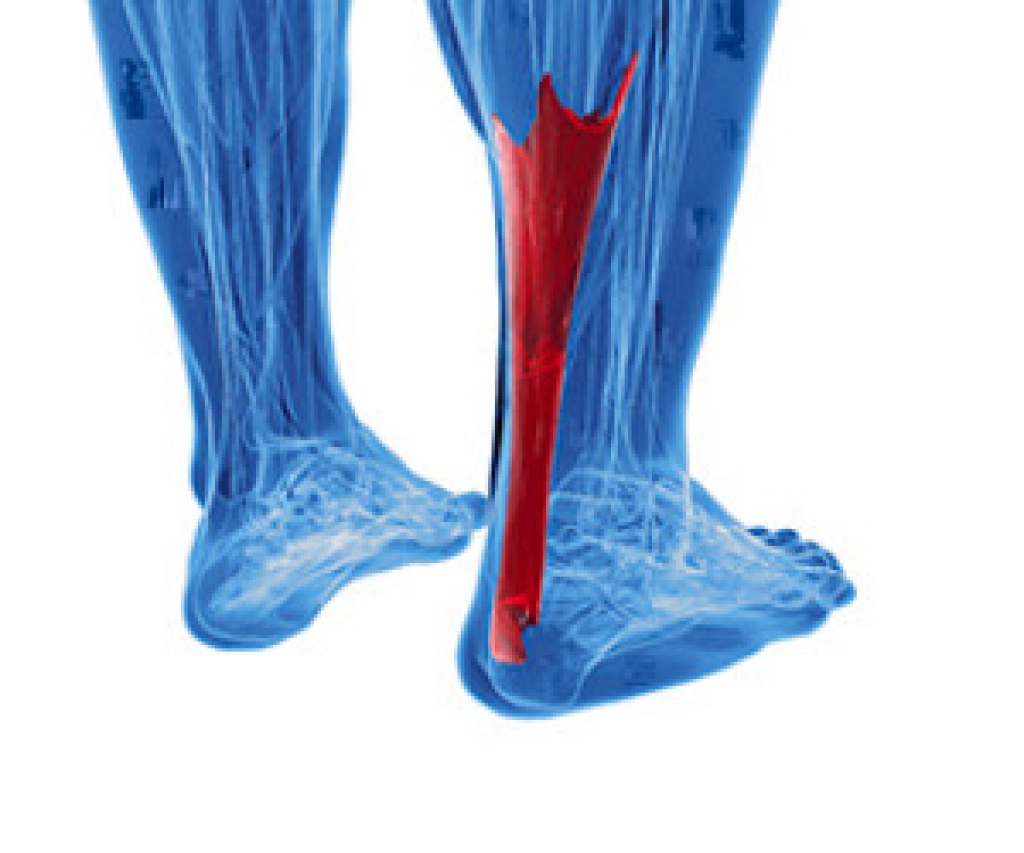

What Happens During an Achilles Tendon Rupture

Achilles tendon ruptures happen when the tendon on the back of the ankle is torn. They primarily occur during activities such as tennis and basketball, which involve pushing off of the ground or sprinting. While the Achilles tendon can tear and may be injured at any age, it most commonly occurs in patients who are in their 30s and 40s. Those who have poor flexibility, an inactive lifestyle, or who only occasionally work out are also at risk for ruptures. Ruptures are often indicated by sudden pain, a sense of being kicked in the back of the leg, a “popping” feeling, and weakness in the heel. Patients who have ruptured their Achilles tendon should consult with a podiatrist for treatment options. Surgery may be necessary to fix the tendon, but time, a cast, and physical therapy may also be used as treatment.

What Is the Achilles Tendon?

The Achilles tendon is a tendon that connects the lower leg muscles and calf to the heel of the foot. It is the strongest tendon in the human body and is essential for making movement possible. Because this tendon is such an integral part of the body, any injuries to it can create immense difficulties and should immediately be presented to a doctor.

There are various types of injuries that can affect the Achilles tendon. The two most common injuries are Achilles tendinitis and ruptures of the tendon.